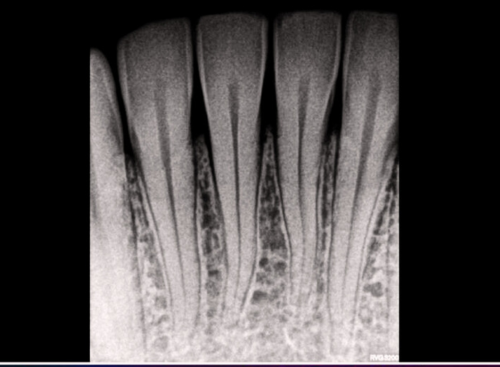

Get a precise consultation with advanced digital X-rays that help us detect issues early and plan the best treatment for your smile.

Our portable X-ray unit allows us to quickly capture diagnostic images during your consultation, ensuring faster evaluations and seamless treatment planning. Whether it’s for detecting cavities, assessing root conditions, or evaluating bone health, our X-ray facility ensures accuracy without delay.

With zero need for repositioning or multiple visits, patients enjoy a more comfortable, time-saving experience while our team gets the detailed data needed for expert care.